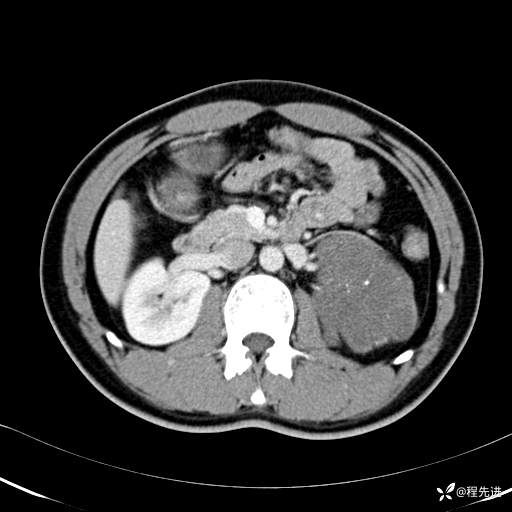

CT平扫:(CT值:平扫,27HU,动脉期,27HU,门静脉期,31HU,平衡期,32HU)

CT增强:

平衡期: